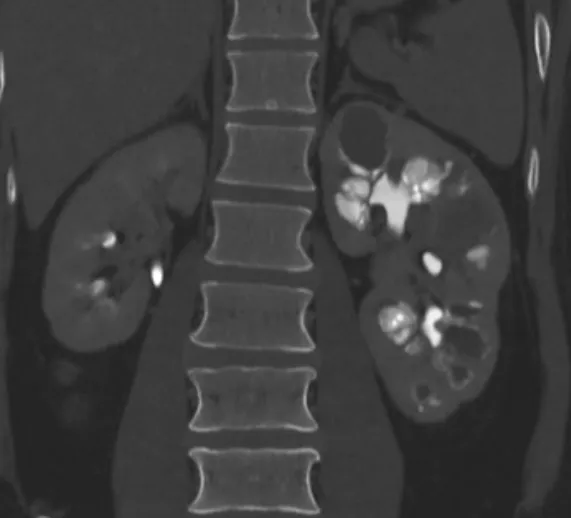

DRC indeterminada ou você esqueceu de fazer o básico? Veja tudo aqui

DRC “indeterminada” raramente é falta de diagnóstico — quase sempre é falta de método. Tempo de evolução, urina bem avaliada, USG renal e história clínica dirigida mudam conduta e evitam erros comuns na prática nefrológica.